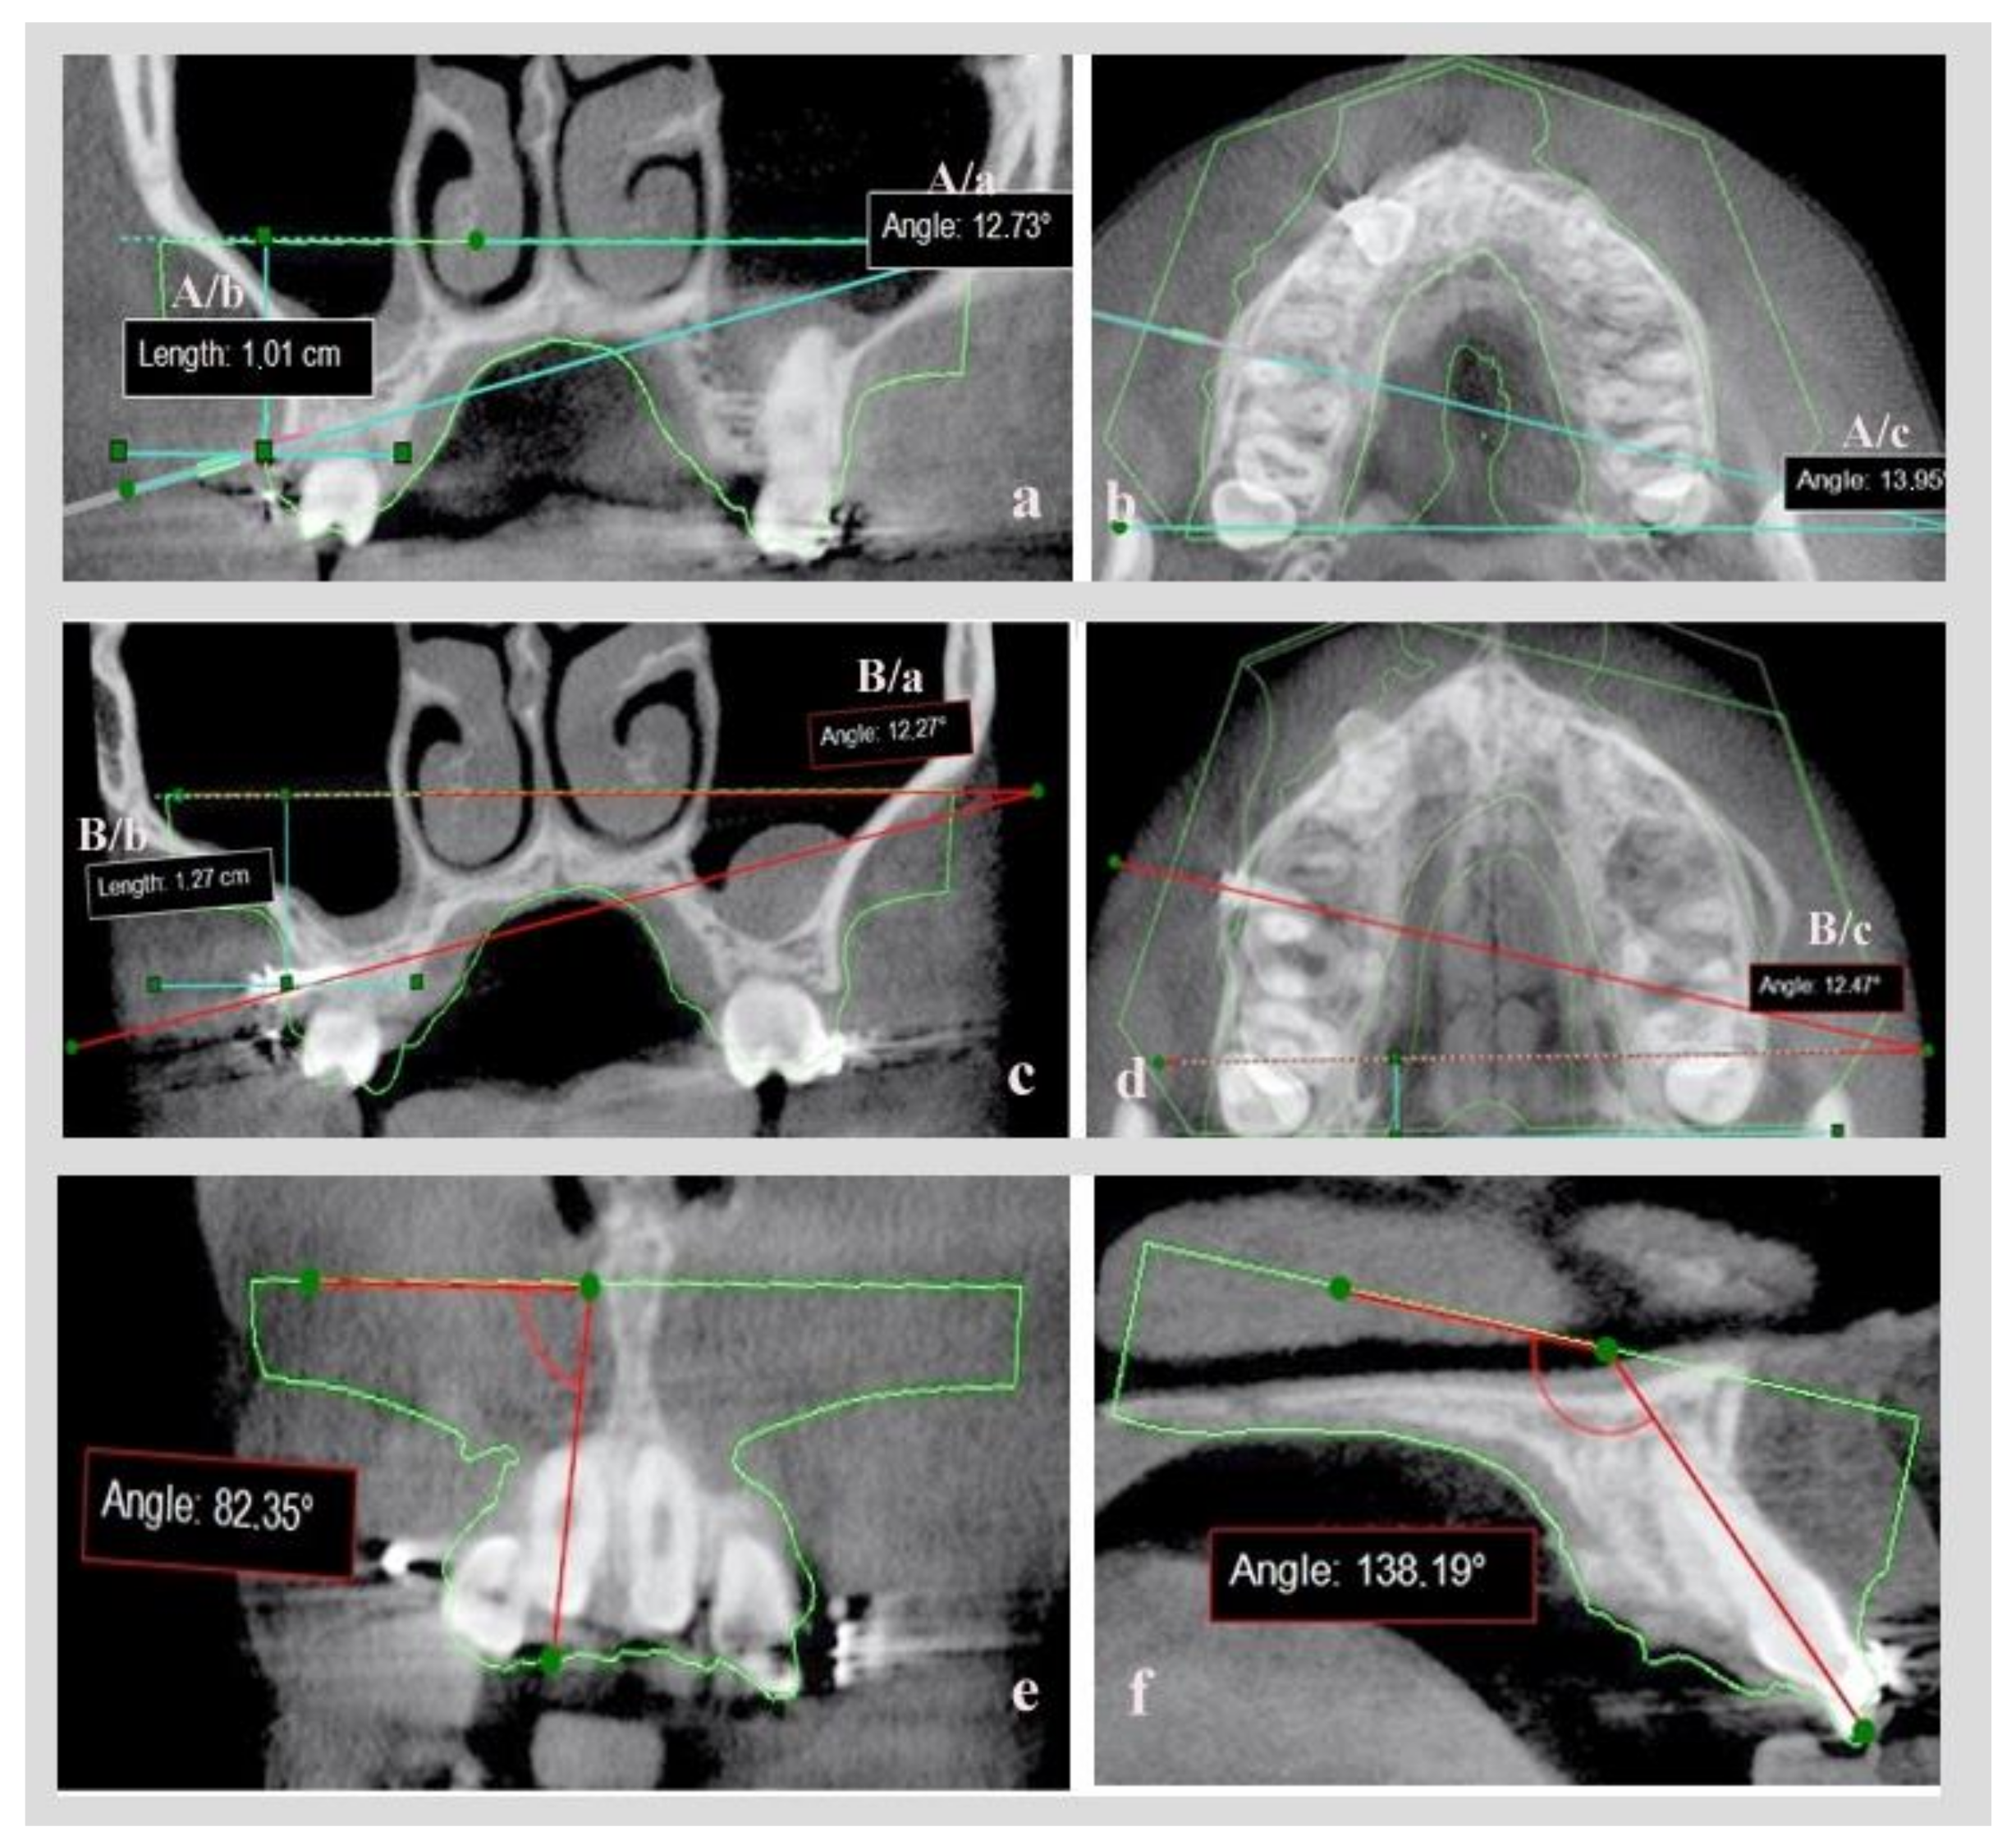

In digital model A, having on-site CBCT images and just the contour of the .stl model, a coronal slice on the point of insertion of the virtual mini-implant in the bone and an axial slice in which most of the mini-implant’s body was visible, were evaluated.

On the coronal slice, measurement was made of the angle defined by the axial line of the virtual mini-implant and the lower base of the .stl model and of the distance of the point of insertion in the bone, to the lower base of the .stl model (Figure 5a: measurement set A/a = coronal angle, A/b = coronal distance). An axial slice measurement was made of the angle defined by the axial line of virtual mini-implant and the lower base side of the .stl model (Figure 5b: measurement set A/c = axial angle).

The same set of measurements were calculated on digital model B with real mini- implants already inserted (Figure 5c: measurement set B/a = coronal angle, B/b = coronal distance, Figure 5d: measurement set B/c = axial angle). By comparing the A and B sets of measurements, and after proper statistical analysis, the accuracy of the mini-implants’ placement could be evaluated after utilization of CBCT or not.

In order to validate the reproducibility and the accuracy of combining the initial .stl and DICOM files before and after mini-implant placement, while creating digital models A and B, two angles were utilized: the angles formatted by the axial line of the central upper or lower right incisor and the base of the initial .stl model in a coronal (Figure 5e) and a sagittal slice (Figure 5f).These were calculated on models A and B and compared, since movement of central incisors was avoided between the initial and the final CBCT.

Figure 5. (a) Coronal slice (measurement set A/a, A/b). (b) Axial slice (measurement set A/c) for evaluating virtual mini-implant’s position. (c,d) Coronal and axial slice for evaluating the real mini-implant’s position (measurement set B/a, B/b, B/c). (e) Angle of axial line of central upper right incisor and the base of the STL model in coronal slice. (f) Angle of the axial line of the central upper right incisor and the base of the STL model in a sagittal slice.